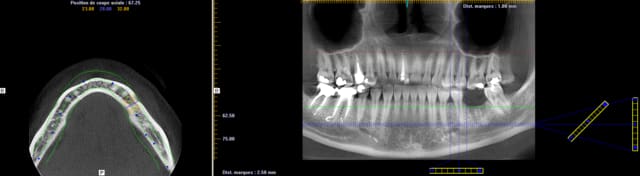

Bon finalement j'ai fait mon choix, cone beam installé hier !

Vatech Ewoo.

Pour moi les plus :

- taille de champ variable: 5*5 8*5 8*8 12.5*8

- vraie combo pano/cone beam

- interface sympa

- artefact métallique limité

- Logiciel d'imagerie et planification implantaire très bien

(pour info c'est une version d'Ondemand3D à l'essaie pour 90j ici:

http://www.ondemand3d.com/Content/Download/Trial.aspx prix du soft environ 5000$)

- budget compétitif

quelques clichés d'essais